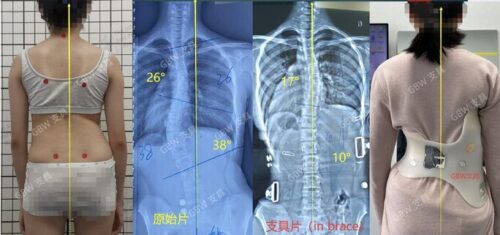

في بعض الحالات، قد تكون درجة الانحناء بسيطة جدًا ولا تتطلب استخدام الحزام، بل المراقبة فقط. هنا يكون من حق الأهل طلب رأي طبي ثانٍ للتأكد من ضرورة العلاج. القرار الأفضل دائمًا هو المبني على تقييم دقيق بالأشعة والفحص السريري.

نجاح الحزام الطبي لعلاج اعوجاج العمود الفقري عند المراهقين لا يعتمد على ارتدائه فقط، بل على تفاصيل دقيقة مثل تصحيح دوران الفقرات الأولى وسرعة هذا التصحيح. متابعة الأهل مع الطبيب، الالتزام بعدد ساعات الارتداء، واستخدام الحزام المصمم خصيصًا لكل طفل، جميعها عوامل تزيد من فعالية العلاج وتمنح الطفل فرصة أفضل لنمو ظهر مستقيم وحياة طبيعية.

التطور الكبير في تصميم الأحزمة الطبية جعل علاج اعوجاج العمود الفقري عند المراهقين أكثر نجاحًا وأقل إزعاجًا. باستخدام تقنيات التصوير الثلاثي الأبعاد والمحاكاة الرقمية، أصبح الحزام أكثر خفة وراحة، ويعطي نتائج أفضل في تصحيح الانحناء والتواء العمود الفقري.